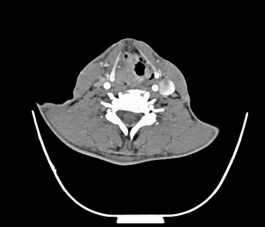

喉癌颈淋巴结转移

声门型喉癌不易发生颈淋巴结转移,声门上型及声门下型则易发生颈淋巴结转移。

常见的还有口咽、口腔、鼻腔鼻窦癌颈淋巴结转移、甲状腺癌颈淋巴结转移等。颈部恶性肿瘤的诊断需要借助详细的病史、全面的体格检查及辅助检查(包括彩超、CT、电子鼻咽喉镜等),最重要的还是要去耳鼻咽喉头颈外科专科就诊。